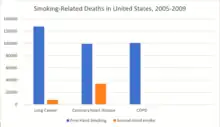

The morbidity of cigarette smoking is nearly 50% with 7 million first-hand smokers and 1.2 millions second hand smokers killed each year[8]. Regardless of active or passive smokers, macrophage accumulation is found in the lungs.[3][5] The diagnostic methods for smoke-related diseases include bronchoalveolar lavage which can also be used for examining smoker's macrophages in addition to augmented inflammatory cells in the alveolar lumen.[1]